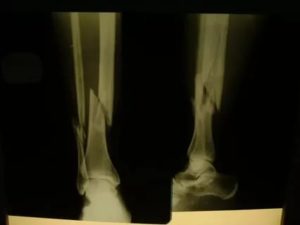

Наиболее часто врачи назначают рентгенологическое обследование и производство снимков. Методика позволяет диагностировать перелом большой и малой берцовой кости. При повреждении нерва показана электронейромиограия.

Если перелом в области мыщелков или оскольчатый показано проведение МРТ. Методика позволяет уточнить вид перелома, особенно если перелом большой берцовой кости без смещения, невидимый на рентгеновском снимке.

Когда происходит повреждение большеберцовой кости, переломы могут случаться в эпифизе, диафизе, либо же случается перелом мыщелков большеберцовой кости.

По расположению линии разлома возможен поперечный, косой перелом или спиральный перелом (иногда врачи именуют этот тип как винтообразный перелом). Травма может иметь закрытый или открытый характер.